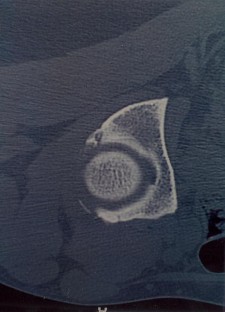

Osteoid osteoma of the acetabulum: a case report

The acetabulum is a very rare location for osteoid osteoma. The diagnosis is difficult and usually delayed because the acetabulum is a rare site for this tumour and clinical signs are non-specific. Reported herein is the case of a 33-year-old woman who had non-specific pain and limitation of range of motion of the right hip. Bone scan, computed tomography and magnetic resonance imaging assessed the diagnosis of osteoid osteoma. Percutaneous resection guided by CTscan was performed and histology confirmed diagnosis. At follow-up, from two years, the patient remains asymptomatic. Osteoid osteoma of the acetabulum has been reported only in 13 cases. It is usually characterised by signs of synovitis. Recently, Computed Tomography guided percutaneous resection of OO has become the treatment of choice.

Fig. 2